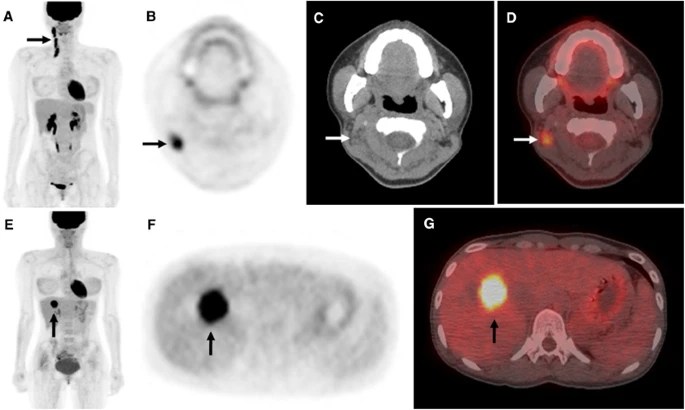

PET-CT combines the functional information obtained from positron emission tomography (PET) with the anatomical details provided by computed tomography (CT). PET utilizes a radioactive tracer, typically fluorodeoxyglucose (FDG), which is taken up by metabolically active cells, such as cancer cells. By detecting the concentration of FDG, PET can highlight areas of increased metabolic activity, indicating the presence of tumors or areas with potential malignancy. The addition of CT imaging allows for precise anatomical localization of these areas, providing a comprehensive view of the tumor and its surrounding structures.

In PET imaging, the standardized uptake value (SUV) is a quantitative measure used to assess the level of FDG uptake within a tumor or lesion. SUV measurement provides valuable information about the metabolic activity of the tumor and helps in characterizing its aggressiveness. Higher SUV values often indicate a higher metabolic rate and increased tumor activity. The SUV measurement serves as an important parameter in cancer assessment and can assist in several aspects, including staging, treatment response evaluation, and predicting patient outcomes.

In head and neck malignancy, SUV values play a significant role in determining the extent and behavior of the tumor. Different malignancies can exhibit varying SUV values depending on their characteristics. For example, a higher SUV value in a head and neck tumor may suggest a more aggressive tumor phenotype and a higher likelihood of metastasis. On the other hand, a lower SUV value may indicate a less metabolically active tumor with a potentially better prognosis.

The specific SUV values for malignancy vary depending on the type of tumor, its location, and individual patient factors. Generally, SUV values above a certain threshold, such as 2.5 or 3.0, are considered indicative of malignancy. However, it is important to interpret SUV values in conjunction with other clinical and imaging findings for a comprehensive assessment.

1. Staging: PET-CT scan is highly valuable in the initial staging of head and neck malignancies. It provides detailed information about the primary tumor, lymph node involvement, and the presence of distant metastases. By accurately determining the extent of disease, including SUV measurements, PET-CT scan aids in treatment planning and prognostication.

2. Detection of Occult Primary Tumors: In some cases, patients may present with cervical lymphadenopathy without an identifiable primary tumor. PET-CT scan, along with SUV measurement, can help locate the occult primary tumor by detecting areas of increased metabolic activity, potentially guiding targeted biopsies and treatment decisions.

3. Assessment of Treatment Response: Following treatment, PET-CT scan, along with SUV measurement, can assess the response to therapy by comparing pre- and post-treatment images. It helps determine the effectiveness of treatment and aids in decision-making regarding further management, such as the need for additional surgery or adjuvant therapy.

4. Detection of Recurrence: PET-CT scan, with SUV measurement, is instrumental in detecting recurrent disease in patients previously treated for head and neck malignancy. It can identify areas of increased metabolic activity, indicated by higher SUV values, that may indicate tumor recurrence, guiding further investigation and appropriate management.